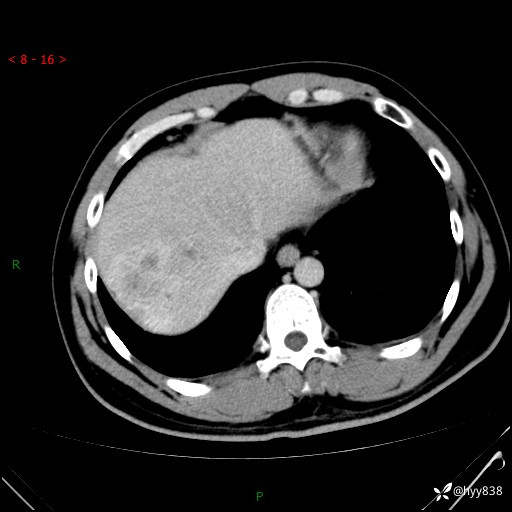

静脉期

延迟期